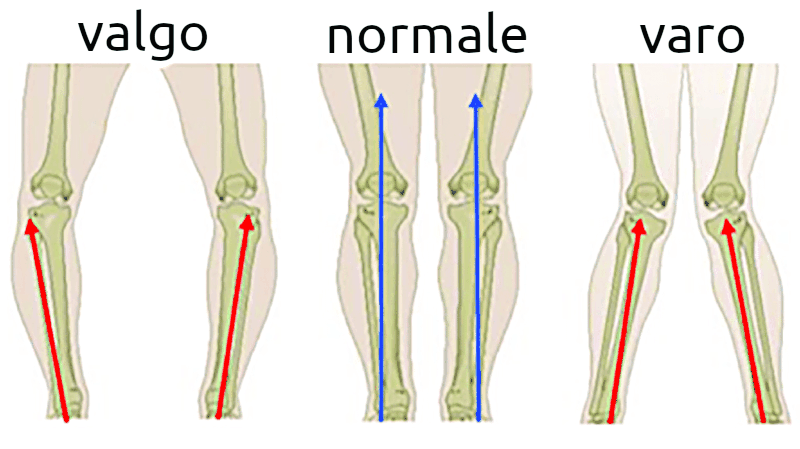

Spesso nel ginocchio artrosico è compresente una alterazione dell'asse femoro-tibiale con due varianti:

ginocchio varo con le cosiddette "gambe a X"

ginocchio valgo con le cosiddette "ginocchio da cavallerizzo"